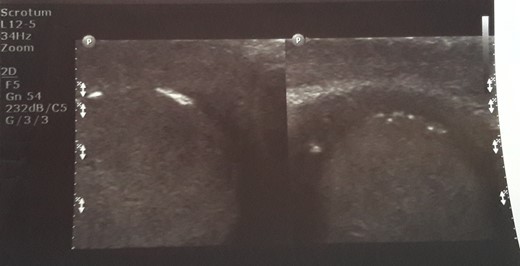

Initial sonographic findings were suggestive of epididymo-orchitis. The testis was well perfused and in normal position (Fig. 1). He was admitted for 3 days to start intravenous anti-inflammatory and antibiotic treatment and discharged under antibiotic treatment. Re-examinations were scheduled to assess treatment. On first reexamination, a week later, edema had subsided and the testis appeared hard, indurated and painless (Fig. 2). Ultrasound was still suggestive of epididymo-orchitis. Nevertheless suspicion for a testicular tumor was raised because of persistence of clinical and sonographic findings. An earlier appointment was scheduled this time. Five days later, at the second reexamination, another ultrasound showed reduced testicular perfusion that reached only the periphery of the testicular parenchyma (Fig. 3). The boy was operated as an emergency. Intraoperatively testis was non-twisted, with normal vas and vessels that ended in a necrotic testicular parenchyma. The testis was dark brown, hard on palpation and no blood came out when incised (Fig. 4). Right orchidectomy was performed. Since the exact cause of testicular necrosis was still unkown at the time of operation a left orchidopexy was performed to protect the only surviving testis from any future risk of torsion. The boy was discharged the next day. Histology showed a case of epididymitis nodosa and ruptured sperm granuloma that caused vascular compression, thrombosis and testicular necrosis (Fig. 5). More specifically, it showed proliferation of small ducts and gland-like structures in the walls of the vas deferens and epididymis in response to fluid and sperm dissection into the interstitium secondary to mechanical obstruction and increased intraluminal pressure. These findings are extremely rare in pediatric patients. The boy had an uneventful postoperative course and was discharged 2 days after surgery able to travel by sea to his home island.

On re-examination a week later, edema had subsided and the testis appeared hard, indurated and painless.